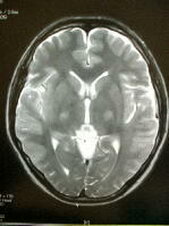

脳の病気で1番怖いものの1つに『くも膜下出血』があります.これは脳の血管にできた『こぶ』が破裂して起こる病気で約半数が命を落とします.脳ドックでは,MRIを用いて未然にこの『こぶ』を発見したり,脳梗塞の前兆や初期の脳腫瘍を発見することを目的としているほか,血液検査,心電図により脳卒中の危険因子をチェックすることを目的としています.当院では日本脳ドック学会のガイドラインに準拠した検査を行っています.現在1ヶ月あたり50-100件の検査実績がございます.万が一異常が発見された場合はご相談の上,適切かつご希望の病院にご紹介いたします.

7,MRI検査(頭部の断層撮影,頭部と頚部の血管撮影)